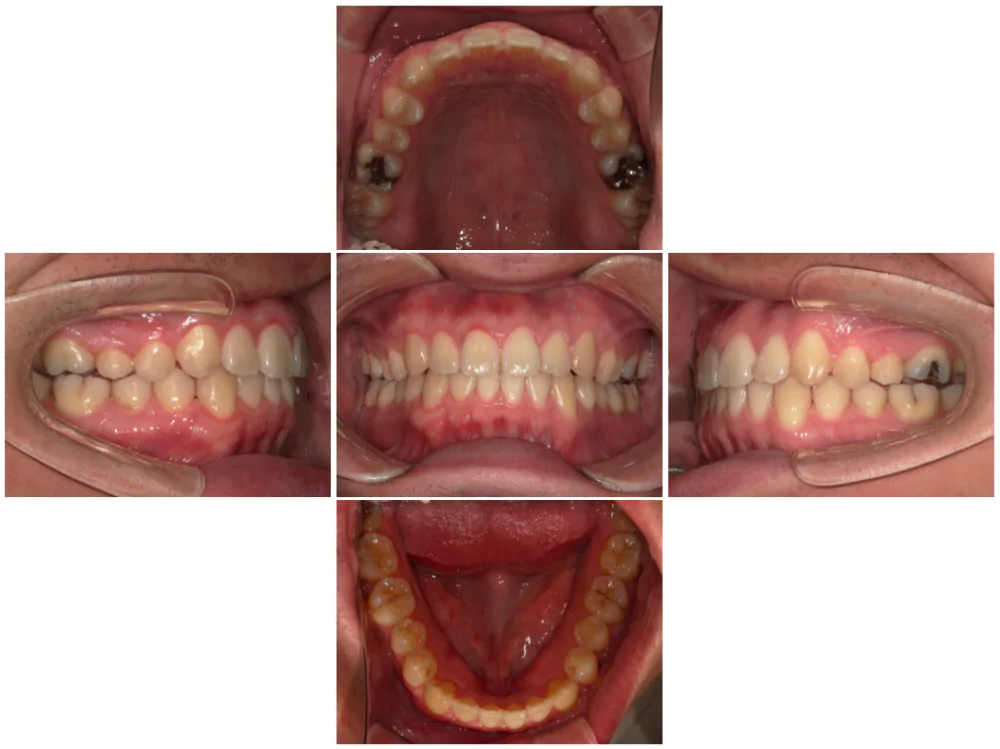

症例3

| 来院時の主訴 | 歯の間の隙間を閉じたい |

| 医院での対応や適用装置 | マウスピース矯正装置を使用して主訴である歯の間の隙間を閉じて改善を行いました。 歯の隙間の原因は飲み込み時に舌を前に出してしまう癖だと考えられましたので、 トレーニングを行い癖も無くなりました。 |

| 通院期間 | 6ヶ月 |

| 通院回数 | 5回 |

| 治療費用総額 | 577,500円(税込) |

| リスクと副作用 | 矯正治療による歯の移動に伴う痛み、歯根吸収、虫歯 |